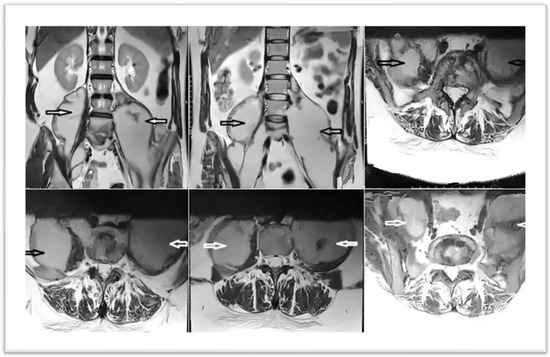

In February 2023, the patient was admitted to the clinic. An MRI of the lumbar spine was performed upon admission. It revealed multiple injuries, but with the preservation of certain structures intact: erosive changes, with association of fluid densities, located at the level of the intervertebral disks (diskitis L4–L5 and L5–S1); multiloculated collections in the psoas muscles bilaterally, 230/79 mm (cc/ll) left and 200/82 mm (cc/ll) right, without clear signs of extension at the epidural space; vertebral bodies, aligned at the anterior and posterior wall; overlying intervertebral disks with preserved height and not exceeding the vertebral contour (Figure 1).

Figure 1. MRI images at admission—sagittal and transverse sections—arrows indicate the two collections, left and right.